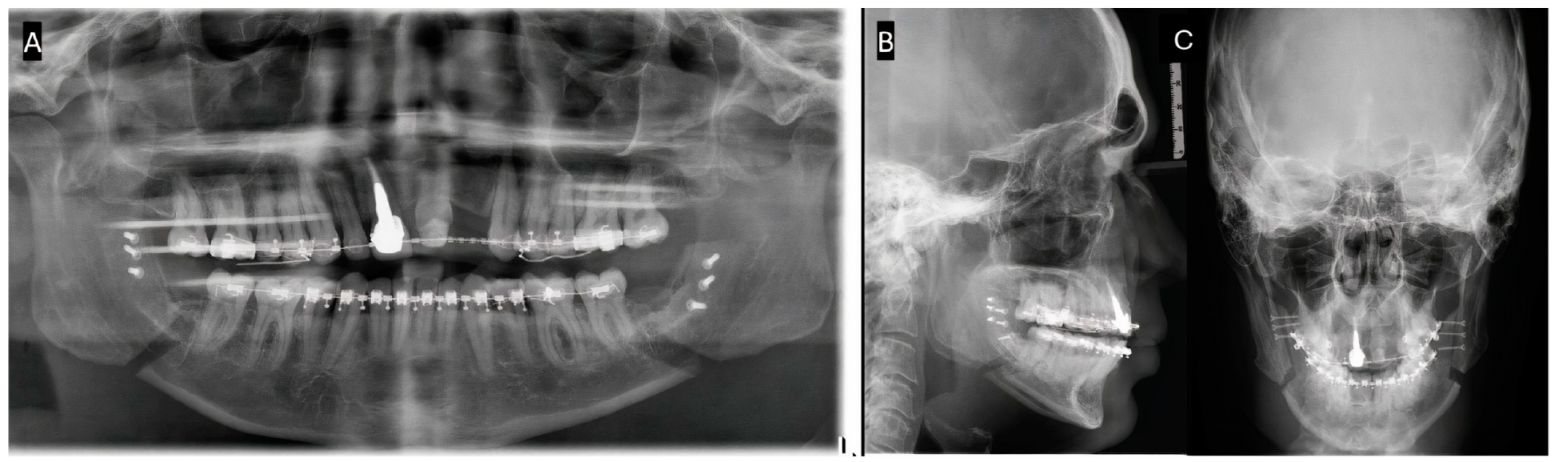

Arteriovenous Fistula with Pseudoaneurysm and Facial Palsy Following Bilateral Sagittal Split Osteotomy: A Case Report

2. Case Report